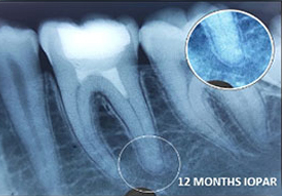

Amanulla -

PRF Mediated REP in 22 with 18 months Follow up

Complete Bony Healing, Calcific Bridge Formed.